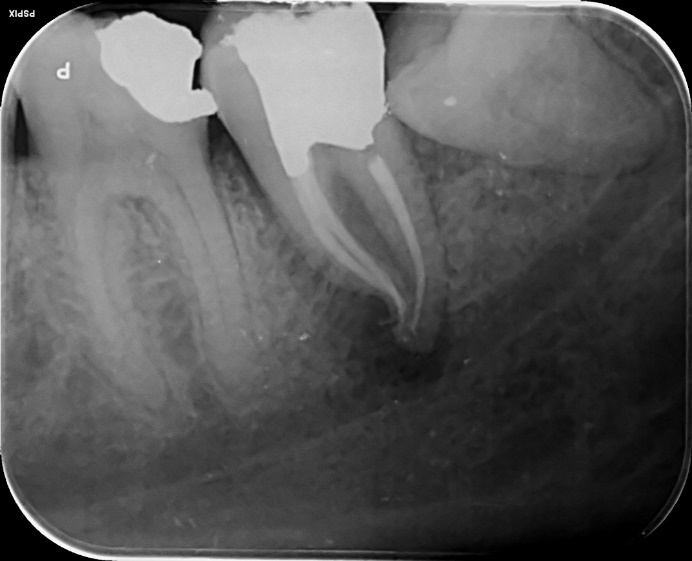

Lower Molar curved root Primary root canal treatment and rebuild